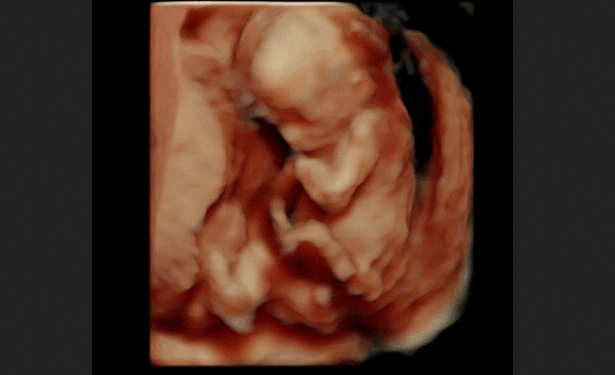

“This is flat out drug dealing. … There is no doctor-patient relationship whatsoever. These are people who are writing these prescriptions and sending them to anybody who asks, don’t know where they’re going, and there is no relationship — period,” Murrill continued. The previous rules governing the prescription of mifepristone required abortion drug manufacturers “to have a contract with a doctor that prescribed these medications, and they had to comply with these elevated FDA rules which required in-person dispensing and ultrasound and post care,” she explained. “All of those things meant you needed an individual personal relationship with a doctor. You don’t have that anymore. And it is illegal to use those pills here for an abortion. So every one of those are illegal abortions being practiced in our state without any medical supervision whatsoever.”

In 2023, then-President Joe Biden and his administration eliminated many of the few remaining safeguards, requiring no in-person physician visits, no physician to prescribe the drug, no dispensing or consuming the drug in-office, no follow-up visit, and no reporting of complications. Murrill called the Biden-era changes “entirely arbitrary.” She explained, “The data has always been there, [warning] that this is dangerous for women. That’s why the protocols are in place in the first place. Women can get sepsis if they have a partial abortion, [and] that happens in a significant number of these cases.” The Louisiana AG explained that abortion drugs can and do cause serious complications, including hemorrhaging and even death, in some cases. “There [are] all kinds of contraindications also for women to not take these pills. That’s why you were required to see a doctor, have an ultrasound, and also have some follow-up care if, in fact, you were using these.”